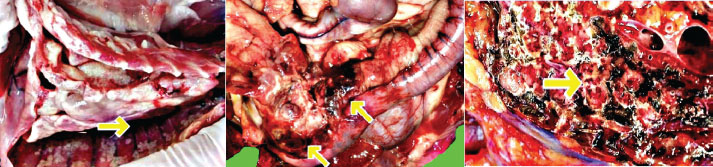

A complete necropsy was performed in accordance with EAZA and AZA standardized protocols (Scaglione et al., 2019) (Supplementary Material S5). Gross examination revealed severe emaciation, dehydration, and yellowish effusions in the abdominal and pericardial cavities. The liver appeared markedly pale and atrophic upon gross examination, with a reduced size consistent with chronic disease processes. The gastrointestinal tract contained undigested ingesta, primarily in the stomach and proximal small intestine, likely due to assisted feeding attempts during the clinical course. Marked icterus was observed in the subcutaneous and visceral adipose tissues. Multiple small (2–4 mm) white fibrinous plaques were distributed on the serosal surfaces of the thoracic and abdominal organs (Fig. 3).

Fig. 3. Gross necropsy findings. Multiple small white fibrinous plaques (2–4 mm) were observed the serosal surfaces of the thoracic and abdominal organs, with evident icterus in the visceral and subcutaneous adipose tissue.